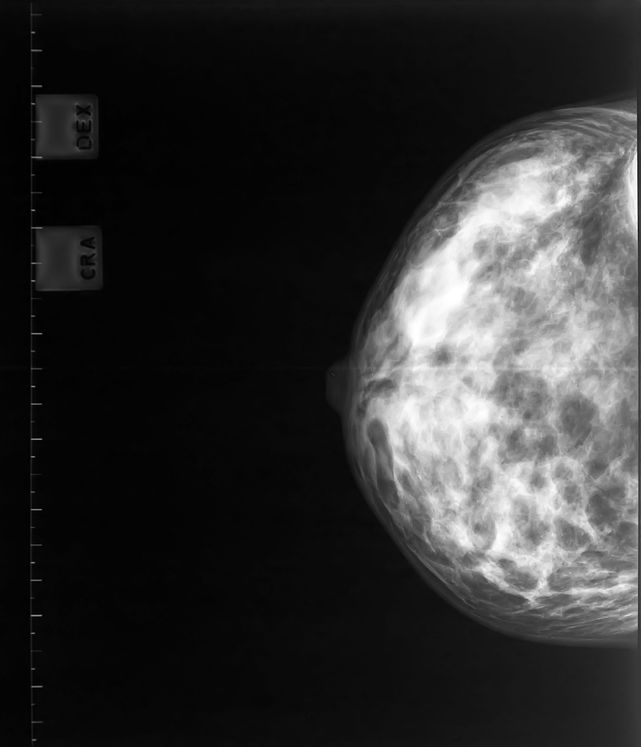

During a mammogram you will place your breast between the two plates of an x-ray machine (pictured right). The breast is then flattened between these plates while the x-ray is taken. Sometimes, this can feel uncomfortable and for some it might feel slightly painful, but it only lasts a few seconds while the x-ray is taken.

The mammogram x-ray identifies lumps or changes in the breast tissue which may develop into breast cancer over time. A mammogram is a very good way of identifying lumps or changes in the breast which cannot be felt by a woman or her doctor.